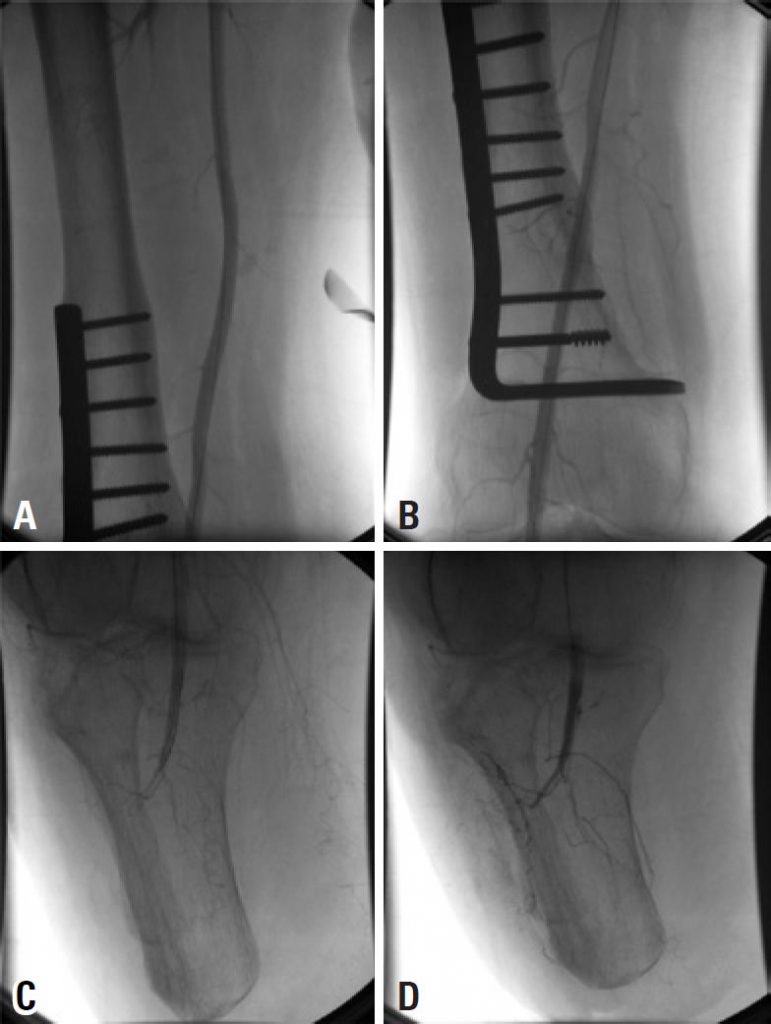

A preservação da articulação do joelho tem grandes vantagens para a mobilidade e a reabilitação de um amputado. Qualquer causa que exija revisão para uma amputação acima do joelho é um grande revés, porque reduz o potencial de reabilitação do paciente. O objetivo aqui foi descrever o uso de trombólise intra-arterial para salvar um coto de amputação abaixo do joelho com isquemia aguda. Homem, 56 anos, procurou pronto atendimento de nosso hospital com histórico de 1 dia de dor aguda em seu coto de amputação infrapatelar direito. A angiografia confirmou oclusão da artéria poplítea. Foi realizada trombectomia farmacomecânica com Aspirex (cateter rotativo para restabelecer o fluxo sanguíneo em vasos ocluídos, removendo material de oclusão do vaso) e ativador do plaminogênio tecidual recombinante. Após 9 anos de seguimento, o paciente permanecia assintomático, capaz de deambulação independente com membro protético. A fibrinólise intra-arterial parece ser um tratamento seguro e eficaz para casos selecionados de coto de amputação com isquêmica aguda.